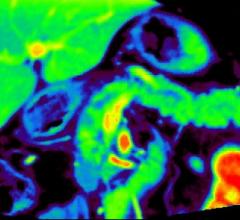

December 2, 2015 — Philips announced IntelliSpace Portal 8.0, the latest edition of its advanced data sharing, analytics ...